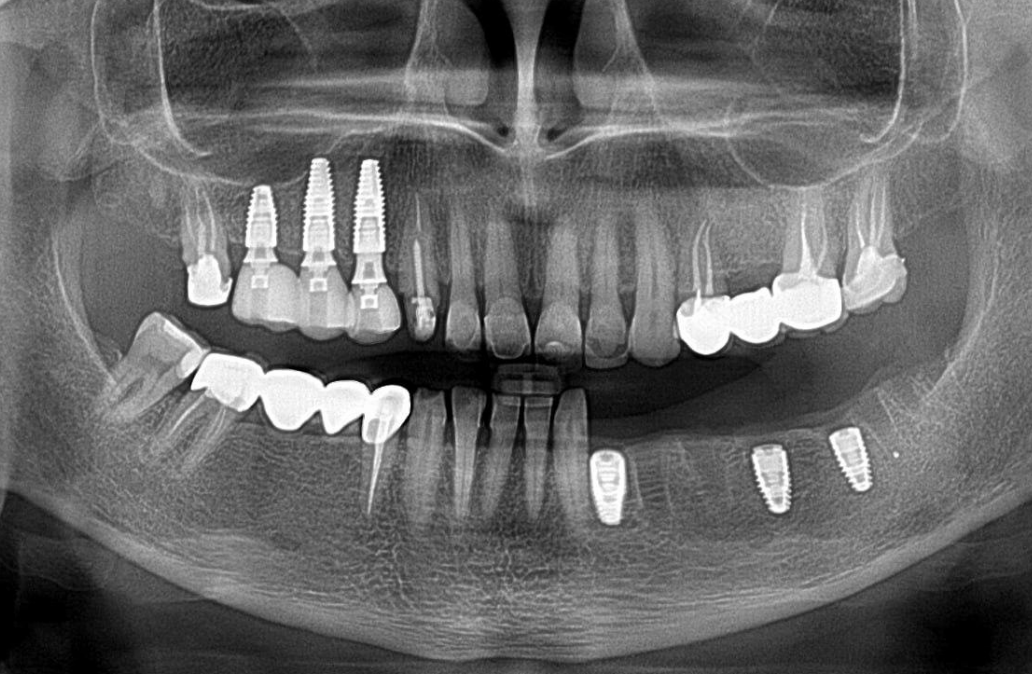

Three Straumann BL® implants with a standard conical connection were placed in positions 14, 15, and 16. Notably, a short implant was selected for position 16 to avoid penetrating the maxillary sinus and perforating the Schneiderian membrane (see radiograph below).

Restorations in the posterior region are subject to high functional loads; using three implants ensures optimal load distribution, favoring a positive long-term prognosis.

The radiograph confirms the integrity of the restoration; marginal bone levels around the implants remain stable.